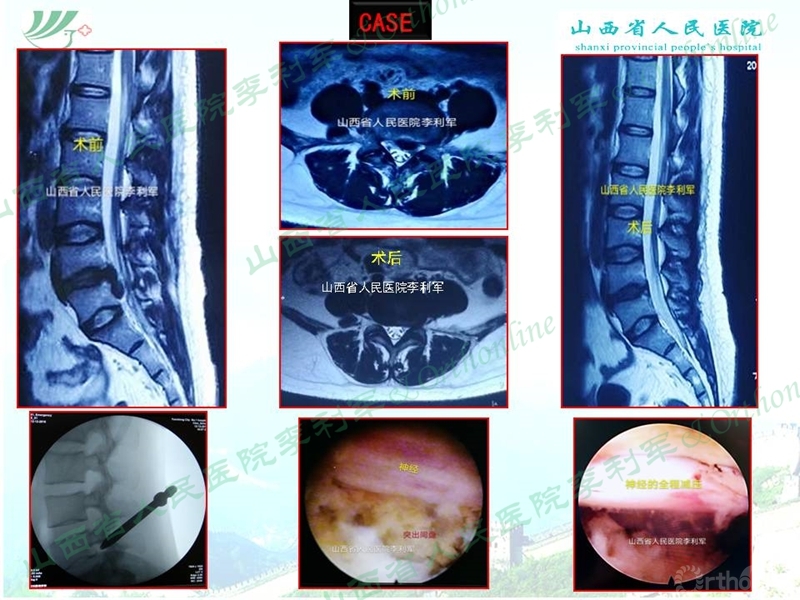

山西省人民医院李利军医生根据自己临床遇到的部分病例,归纳常见的特殊腰椎间盘突出为:高度游离间盘突出,伴有钙化的间盘突出,巨大间盘突出,复发间盘,极外侧间盘突出,易误诊为肿瘤的间盘突出,伴有神经变异的间盘突出等;并根据自己的临床体会对以上特殊类型间盘突出的孔镜治疗作了一些技术总结,以期达到抛砖引玉的作用,并等到大家的批评和指导。

椎间孔镜治疗特殊类型腰椎间盘突出症